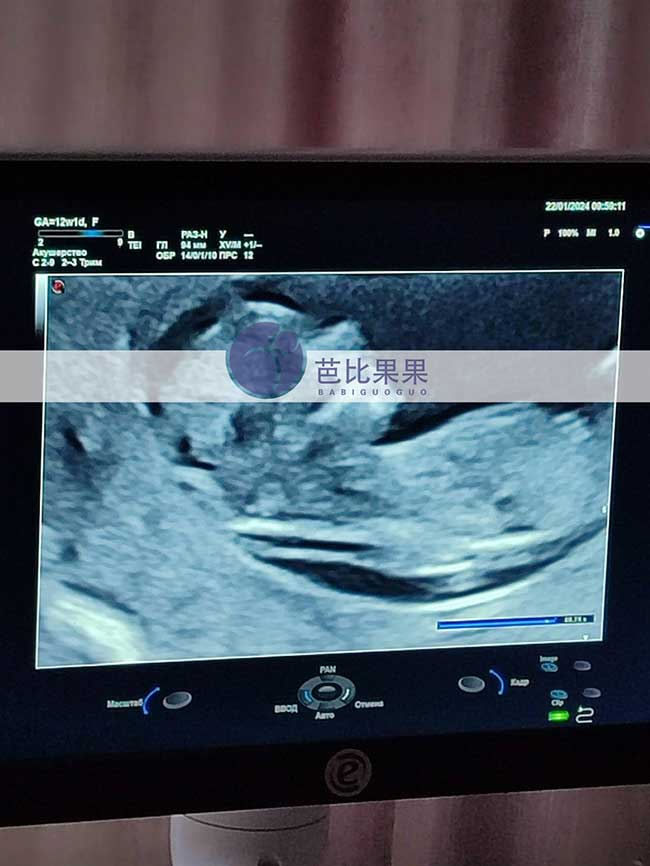

S女士家的乌克兰试管妈妈来做孕12周B超检查

S女士家的乌克兰试管妈妈来做孕12周B超检查,恭喜他们的二胎宝宝已经胎稳啦